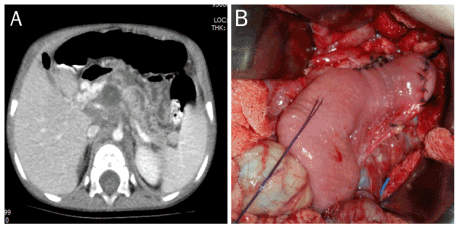

A-2-year old, 8000gr (<3p) female was admitted with abdominal pain for 45 days without history of trauma. She had been treated for bilateral pleural effusion and pancreatic cysts at another institution with no improvement. Her physical examination was unremarkable. Laboratory tests were as follow: Hb: 8mg/dl, CRP: 167mg/dl, Amylase: 161 U/L, Lipase: 355U/L. Computed tomography revealed, dilated pancreatic duct and 5x6cm in sized peripancreatic fluid (Figure 1A). Concomitantly venous cavernous transformation was reported in the portal hylus. Percutaneous drainage catheter was inserted, and parenteral nutrition was given. Sphincterotomy was done via ERCP (endoscopic retrograde cholangiopancreatography). She was discharged on 20th day uneventfully. Unfortunately, she was readmitted 2 weeks later for abdominal pain and feeding intolerance. Ultrasound revealed peripancreatic fluid and cavernous transformation of portal vein. Laboratory tests were as follow: Amylase 189U/L, Lipase 1000U/L,Hb: 7.4mg/dl. Magnetic Resonance Imaging revealed bilateral pleural effusion and dilated pancreatic duct with peripancreatic edema and fluid collection. Bilateral percutaneous drainage was performed. She was considered having relapsing pancreatitis. Modified Puestow procedure (lateral pancreaticojejunostomy) was performed (Figure 1B). Post-operative period was uneventful. Three weeks later, her improvement in nutritional status, and gaining weight (9300gr) was observed. Six months later she was free of symptoms and 12500gr (25-50p) in weight, Amylase and Lipase were normal in limit. She referred for regular gastroenterological follow-up for persisted portal venous cavernous transformation.

Figure 1A. Marked dilated pancreatic duct and regional fluid collection B. Performed modified Puestowprocedure